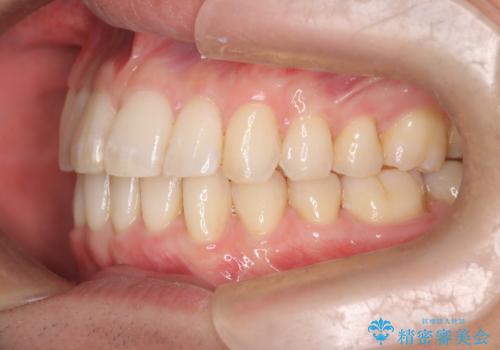

前歯の重なりとガタガタをマウスピースで改善した症例

抜歯は必要なく、マウスピース矯正にて治療を行っています。

見た目、嚙み合わせ及び、治療期間や施術内容に大変ご満足いただきました。